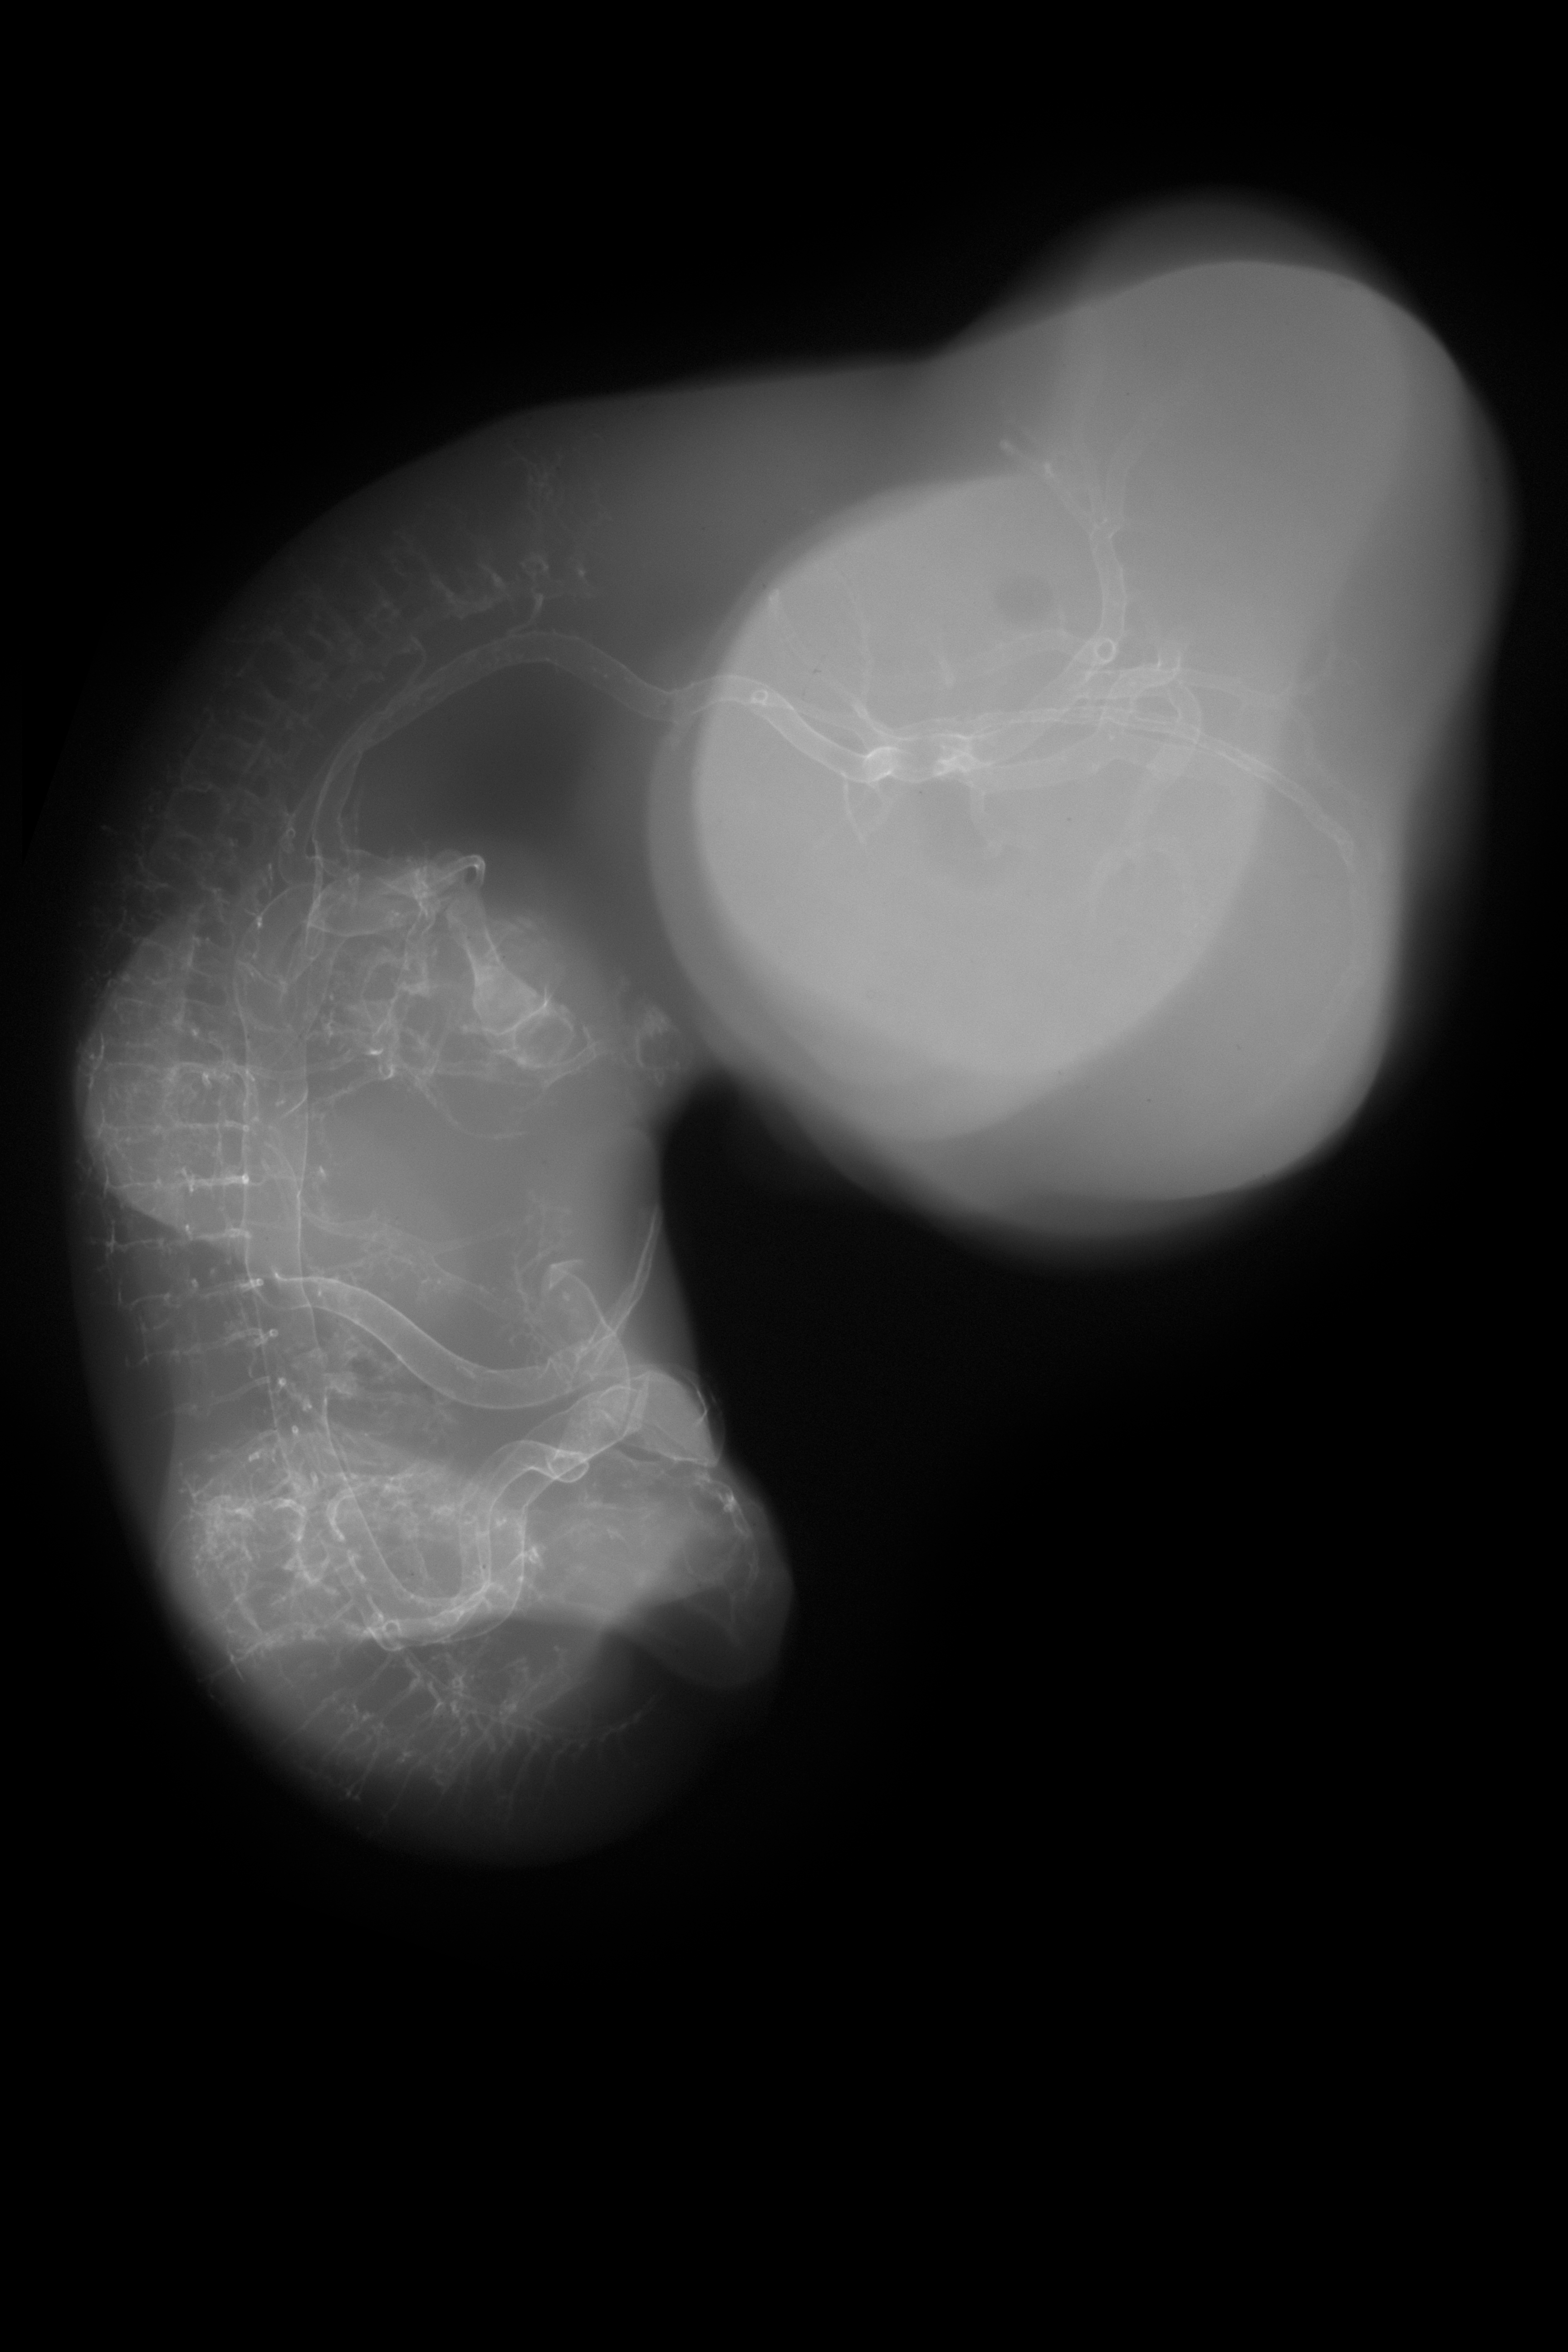

Chick Embryo Microangiography

Hamburger-Hamilton (HH) Stage 29 (approx. 6 - 6.5 days)

X-Ray Micrographs